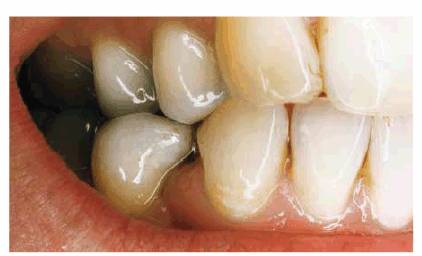

PROBLEM: This 25-year-old actress and model presented with an oversized

maxillary central incisor that had been crowned to close a central diastema

(see Figure 23-15A). Note the extraordinary amount of space

occupied by the left central incisor.

Figure 23-15A: This 25-year-old actress was unhappy with the result obtained with closing her wide diastema with a single central crown. Note the gingival inflammation caused by the overbuilt crown.

TREATMENT: The porcelain crown on the left central incisor was removed,

margins were redefined, and the right central incisor was prepared for a full

porcelain crown. However, if restored today, the right central incisor could

have been more conservatively treated with a porcelain laminate or composite

resin bonding. It was important, in this case, to construct temporary crowns

that would esthetically balance the space and provide the dentist and

technician with a guide for construction of the final restoration. It was felt

that two central incisors were adequate to restore the anterior space. Note the

tissue health around the temporary restorations, but stained acrylic, after 3

weeks of placement (see Figure 23-15B). Final restorations are shown in Figure 23-15C. Note that highlights, vertical lines, and

texture are emphasized to give the illusion of a tooth appearing longer and

narrower than it actually is. The effect can be appreciated by comparing before

and after photographs (see Figures 23-15A, and 23-15C). Note the horizontal highlights in the extra-wide

crown on the left central incisor (see Figure 23-15A) and the vertical emphasis on the new central

incisors (see Figure 23-15C). Figure 23-15D shows the lasting esthetic result 9 years

later.

Figure 23-15B: Following conservative periodontal therapy, interim crowns were placed on both central incisors.

Figure 23-15C and D: Comparison of before and after treatment, which consisted of two all-ceramic crowns, shows a more esthetic result and acceptable tissue health. (C) Crown placement shows an esthetically pleasing result. (D) Nine years later, the esthetic result has been maintained.

RESULT: The original mistake made in this case was to try to close a

diastema between central incisors by altering only one. Unless both central

incisors share restoration of the diastema, or if the single central incisor is

not reduced on the distal to maintain an equal mesiodistal dimension with the

adjacent central incisor, the result will be poor. The most realistic result in

treating a diastema comes from a symmetric approach. This means bonding,

laminating, or crowning two, four, or even several teeth to balance the existing

space.